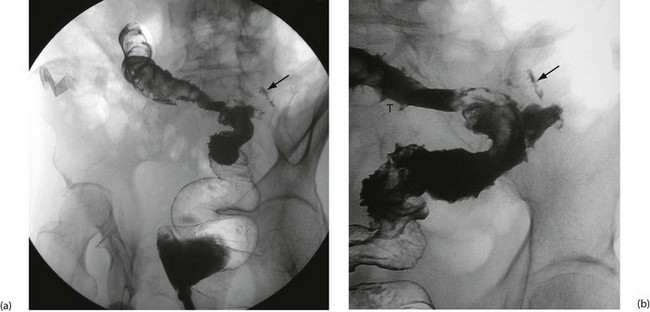

Colonoscopy enables a histological diagnosis to be obtained in colonic disease, and also allows biopsies of terminal ileum to be taken, which are often diagnostic. Barium ‘follow-through’ is the traditional method of examining small bowel but better images are sometimes obtained by controlled instillation of barium into the duodenum via a nasogastric tube. Typical radiological appearances of Crohn's disease include narrowing of the lumen due to mural oedema and fibrosis, nodularity and cobblestoning of the mucosal surface, deep fissured ulceration extending into the muscular wall, spiky ‘rose thorn’ ulcers and possibly evidence of fistula formation. Radiological changes in small and large bowel are shown in Figures 28.9 and 28.10. Note that large bowel abnormalities on barium enema may be difficult or impossible to distinguish from ulcerative colitis.

Appearances of Crohn's colitis are shown in Fig. 28.10.